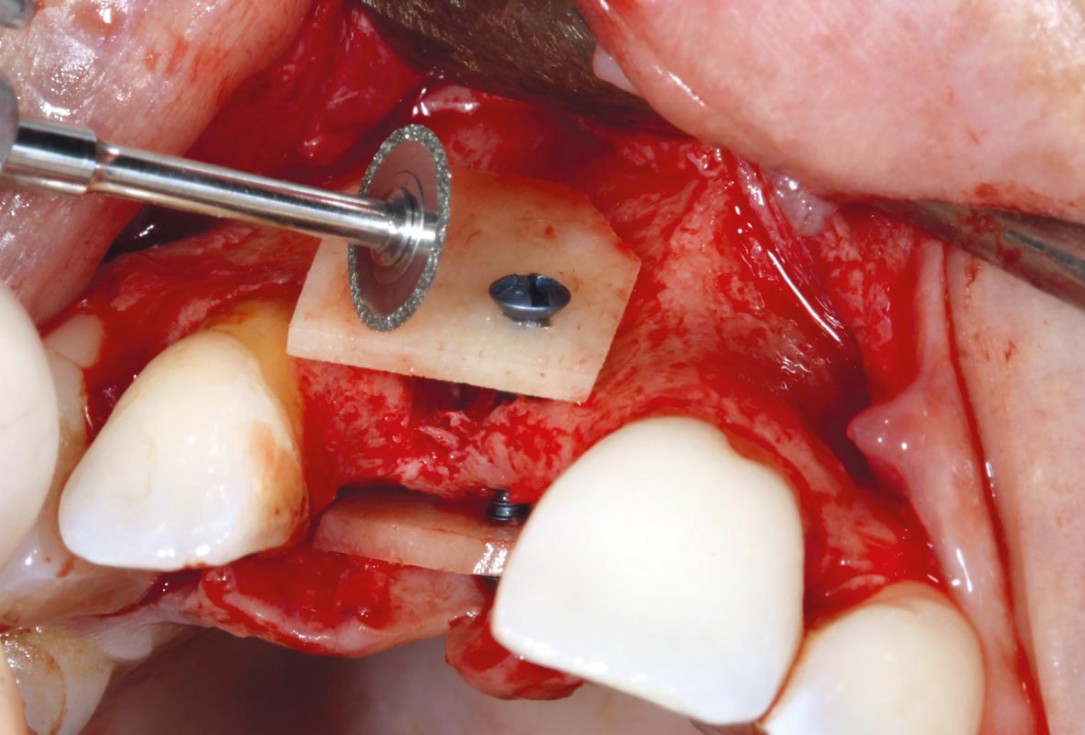

Bone defect in area 11-21 due to two lost implants (periimplantitis) after 15 years of function